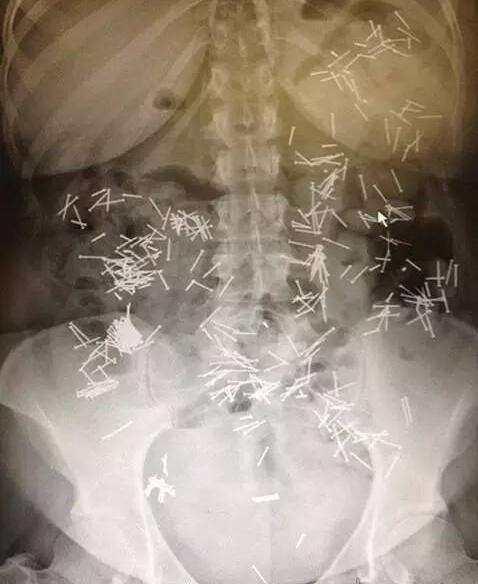

自杀吞入了很多钉子,大夫也不用救了